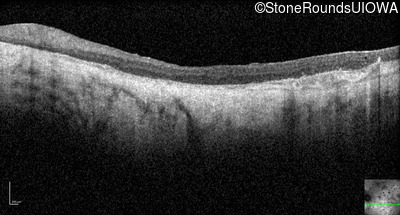

Optical Coherence Tomography - Right - Light Perception

Exemplar / OCT Stack

Optical Coherence Tomography - Left - Light Perception